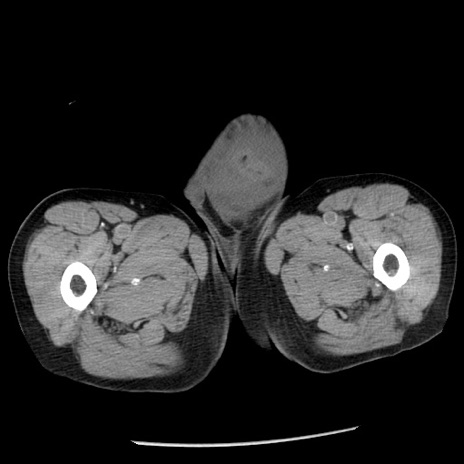

症例26(横断像)

【症例】80歳代男性

【主訴】嘔吐

【現病歴】昨晩2回嘔吐あり、今朝になっても嘔吐あり。来院。

【既往歴】胃潰瘍

【身体所見】意識清明、BT 37.6℃、BP 166/95mmHg、HR 100bpm、SpO2 97%、腹部:平坦・軟、腸蠕動音聴取良好、圧痛なし。

【データ】WBC 21900、CRP 1.46